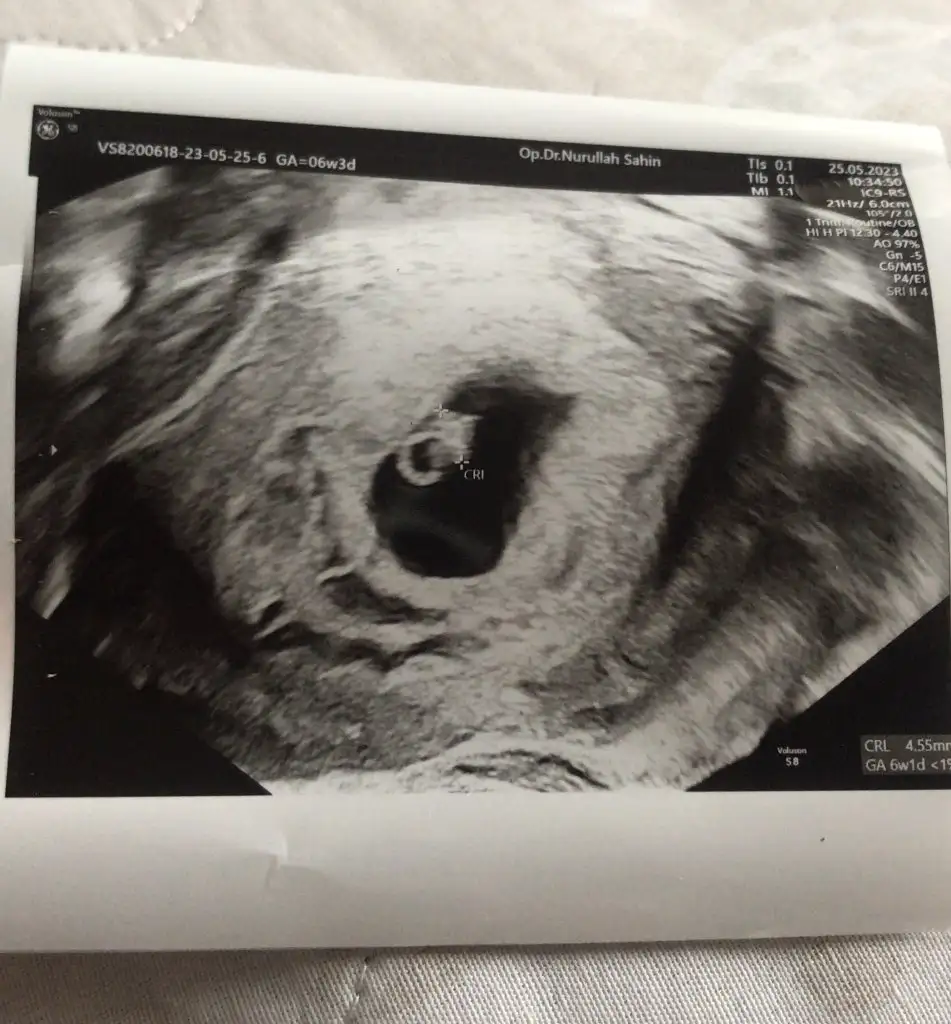

20230525_171422.webp

Kızlar sizce kesenin sol altındaki yuvarlak nedir, ilk ultrasonda da vardı daha küçüktü